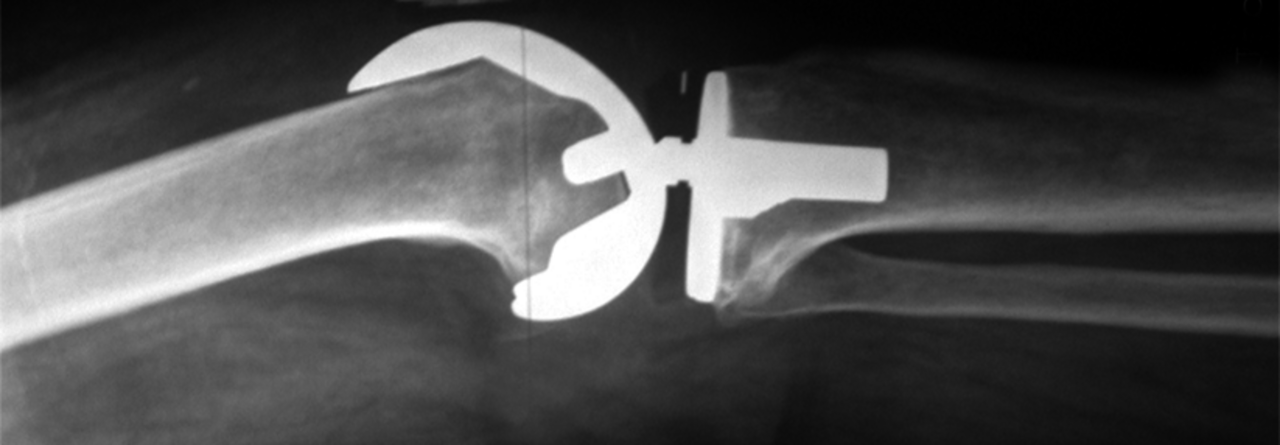

Sämtliche beweglichen Einheiten der Prothese müssen entfernt und ersetzt werden, um den Bakterien die Angriffsfläche zu entziehen. Sämtliche beweglichen Einheiten der Prothese müssen entfernt und ersetzt werden, um den Bakterien die Angriffsfläche zu entziehen. © wikimedia/Fpjacquot~commonswiki

Grundsätzlich geht das, doch in dieser Studie war das Ergebnis enttäuschend: In 42 % der Fälle versagte die konservative Behandlung – nach im Median 62 Tagen. Als Ursache vermutete die Referentin unter anderem ein zu zaghaftes Débridement. Denn die gründliche Wundreinigung ist für die Sanierung des periprothetischen Infekts unerlässlich. Außerdem müssen sämtliche mobilen Teile der Endoprothese ausgetauscht werden, um den Bakterien ihr Versteck zu nehmen.